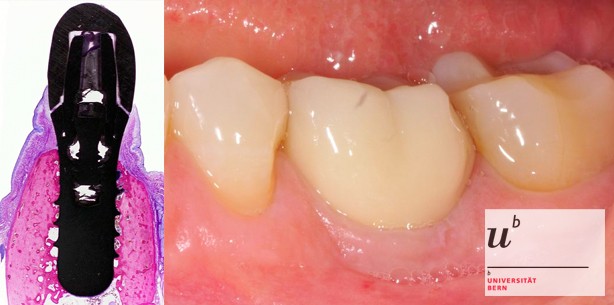

Foto: Foto: Uni Bern

Forschende der Zahnmedizinischen Kliniken (ZMK) Bern konnten in einer umfangreichen Langzeitstudie aufzeigen, dass bei der Routinebehandlung von Zahnimplantaten kaum Komplikationen auftreten und das Risiko für die Patienten somit gering ist.

Um zu prüfen, wie zuverlässig diese Zahnimplantate sind, hat eine Forschergruppe der Zahnmedizinischen Kliniken (ZMK) Bern eine Langzeitstudie durchgeführt, die nun in der international führenden Fachzeitschrift «Clinical Implant Dentistry and Related Research» publiziert wurde. Die Studie der ZMK zeigt, dass Behandlungen mit Zahnimplantaten eine hohe Zuverlässigkeit mit einer geringen Komplikationsrate aufweisen.

Die Studie mit einer Laufzeit von zehn Jahren umfasste mehr als 300 teil-bezahnte Patientinnen und Patienten, bei denen Ende der 90er Jahre einzelne oder mehrere Zähne durch insgesamt 511 Implantate ersetzt worden waren. Dabei wurden Titanimplantate mit einer damals neuen mikrorauen Oberfläche verwendet, die noch heute eingesetzt werden. Die Nachkontrolle dieser Patienten ergab, dass über diese Zeit lediglich sechs Implantate nicht gehalten hatten, was einer Verlustrate von 1.2 Prozent entspricht. Weitere 1.8 Prozent der Implantate zeigten während dieses Zeitraums eine biologische Komplikation in Form einer Infektion.